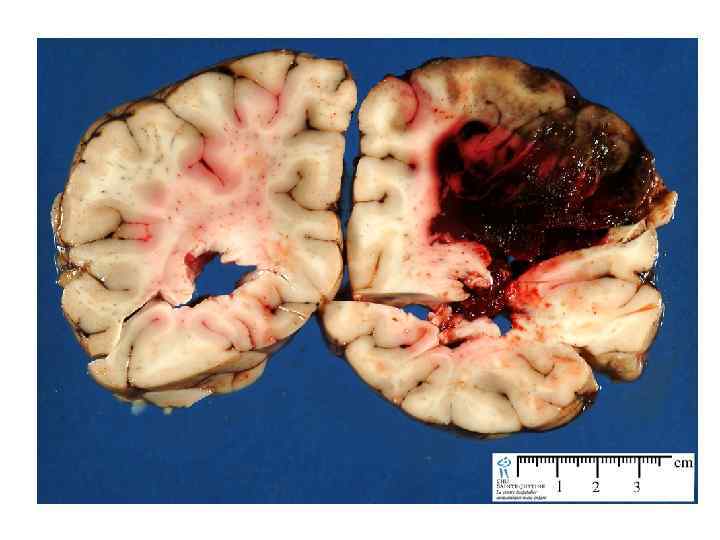

Артериовенозные мальформации • Наблюдаются у 4% популяции, но только у 12% наблюдаются клинические проявления • 38 -70% манифестируют в виде кровоизлияний • Другие симптомы: обмороки, головная боль, эпилепсия, неврологический дефицит